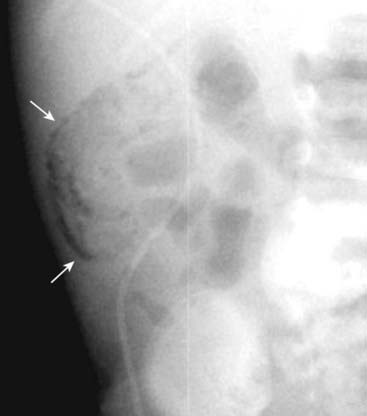

image

Figure 15-13 Pneumatosis cystoides intestinalis.

Axial CT scan of the upper abdomen windowed for lung technique shows a cluster of air-containing cysts (solid white arrows) associated with the left colon, characteristic of pneumatosis cystoides intestinalis, a rare but benign condition in which air-containing cysts form in the submucosa or serosa of the bowel.

Figure 15-14 Necrosis of bowel from mesenteric ischemia.

Axial CT image of the pelvis demonstrates multiple loops of bowel with punctate collections of air throughout their walls consistent with pneumatosis (solid white arrows). The patient had widespread ischemia of bowel from mesenteric vascular disease. Pneumatosis that results from bowel necrosis is an ominous sign.